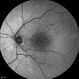

- radiation maculopathy, radiation retinopathy

- Solmaz Shahmohammad, Negah Eye Center, Tehran

- Heidelberg Spectralis

- Mid arteriovenous phase FA image of the left eye of a 65-year-old man with radiation maculopathy and retinopathy.